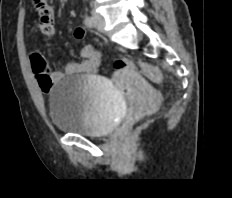

Мультиспиральная КТ мочевого пузыря является частью протокола обследования органов малого таза. Это высокоинформативный рентгенологический метод исследования, позволяющий детально визуализировать мочевой пузырь, нижнюю часть мочеточников, внутренние половые органы, прямую кишку.

Зачастую подобное исследование проводится при мочекаменной болезни (МКБ) для выявления конкрементов, определения их положения, размеров и плотности. Локализация конкремента существенно влияет на терапевтическое лечение МКБ, а наличие дивертикулов стенки мочевого пузыря на возможность самостоятельного выхода камня.

Также при данном исследовании возможно выявить утолщение стенки мочевого пузыря, что при диффузных изменениях может соответствовать проявлениям цистита, а локальные или неравномерные утолщения – характеризовать патологический процесс обусловленный новообразованиями.

Для улучшения визуализации патологических образований, в частности, при подозрении на опухолевый процесс, проводится внутривенное болюсное контрастирование. Методика контрастного усиления основана на введении в вену контрастного препарата, который в большей степени накапливается в патологически измененных участках и обеспечивает их яркую визуализацию на фоне здоровых тканей. Контрастирование дает возможность определить врачу границы опухоли, оценить степень прорастания в соседние органы и ткани, выявить опухоли минимальных размеров (как первичного, так и метастатического характера).

Мультиспиральная КТ используется для диагностики аномалий развития мочевого пузыря, травматических повреждений, воспалительных заболеваний и опухолевых процессов органов малого таза. Преимуществами данного исследования является высокая скорость сканирования и доступная цена. Однако в ряде случаев может быть более предпочтительно выполнение магнитно-резонансной томографии, которая обладает высокой чувствительностью и информативностью для обследования органов и мягких тканей малого таза. В клинике «Доступная медицина» обследование мочевого пузыря входит в протокол МРТ малого таза и его можно пройти на нашем современном оборудовании экспертного уровня